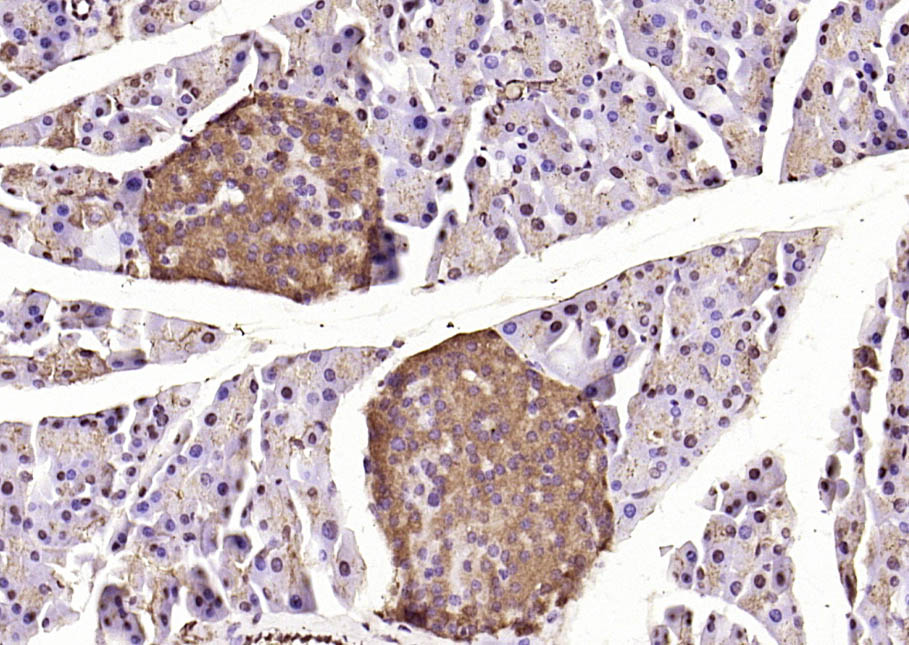

| 产品应用 | WB=1:500-2000, IHC-P=1:100-500, IHC-F=1:100-500, ICC/IF=1:100-500, IF=1:100-500, Flow-Cyt=1ug/Test Not yet tested in other applications. |

| {IHC-P} | {1:100-500} |

[IF={{ 4.2 }}] {Qiong Ma. et al. A Preliminary Study on Quantitative Analysis of Collagen and Apoptosis Related Protein on 1064 nm Laser-Induced Skin Injury. BIOLOGY-BASEL. 2024 Apr;13(4):217} {IHC} {Pig}